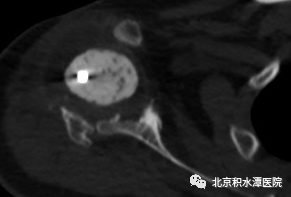

术后患者复查CT,见肩胛盂骨性重建良好。但为解决现有假体长度不足的问题,此次术后,蒋协远教授、黄强主任医师就带领团队医生与工程师团队进行了反复沟通,开始设计并定制合适的反肩假体。按健侧长度计算,肱骨近端骨缺损约8厘米,起初还在肿瘤型假体和APC方式间反复讨论,最后决定采用定制反肩假体结合异体骨(APC)的方式进行处理,同时还定制了相应长度的异体骨,以更好地恢复上肢长度和三角肌张力。

2022年8月18日,患者再次回到北京积水潭医院,蒋协远教授带领黄强主任医师和查晔军副主任医师、公茂琪主任医师等为患者进行了APC反肩置换手术治疗。术中见肩胛盂骨性结构重建良好,取出螺钉,顺利安装肩盂侧反球假体。并反复通过测量和软组织张力判断,确定了异体骨长度,安装肱骨侧假体后,以异体骨板捆扎保护,手术过程顺利,拍片见肩关节假体位置满意。